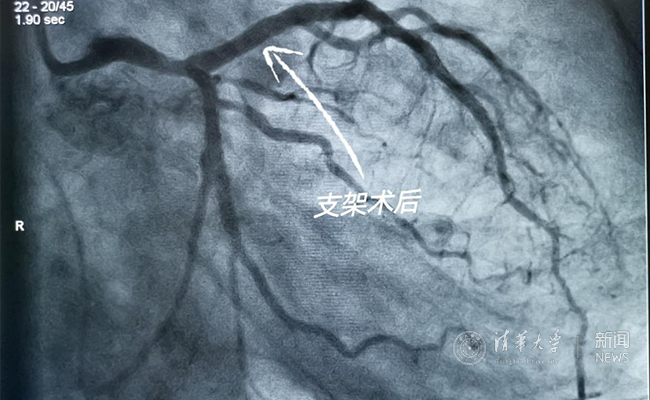

2019.05国产冠脉生物可吸收支架在星空体育第一附属医院正式启用

作为北京地区首家正式引入国产冠脉生物可吸收支架单位,5月20日,星空体育第一附属医院(北京华信医院)心脏中心主任苗立夫团队顺利完成该院首例生物可吸收支架植入。